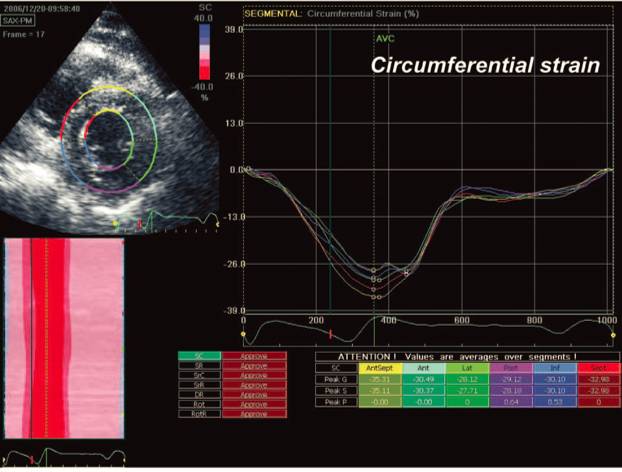

AF导管消融改善心功能

[16]